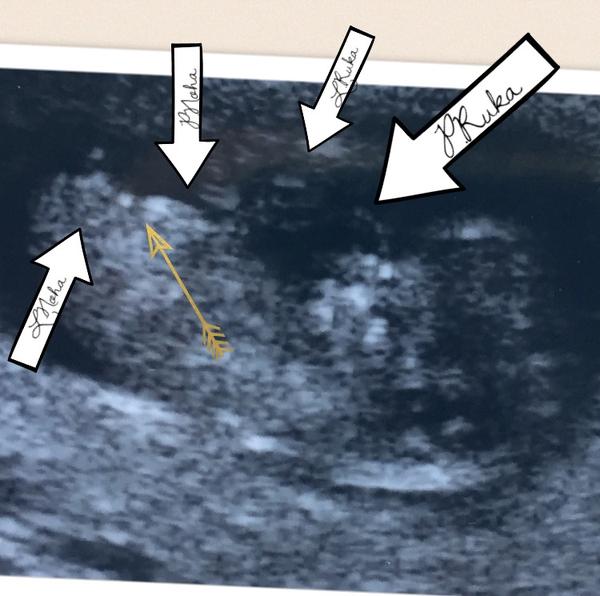

@mariejosef on tam hrbolek není, jsem se ptala dr. Že to je jako dobře vidět ten hrbolek a ona, že to je noha a ne hrbolek, tak mi to popisovala, tak teď jsem to na rychlo jen v tel označila kde co je. Prcek je jakoby bokem dozadu spíš a má právě nožky od sebe, ta jedna "pravá je vidět jakoby vidět pokrčená celá jen chodidlo ne a druhá je koleno směrem dopředu, takže to vytváří ten kloub ten "trojuhelník" a pak zbytek nohy nahoru. Když fotku hoooodně přiblížíš, tak je tam dobře vidět tvar pánevní kost😉a podle toho už si domyslíš, kde právě má být pohlaví. Taky jsem na první pohled myslela, že je prcek jakoby z profilu a je to pindik. Na to mi řekla, že teda jedna to ještě v 10+5 vypadá pohlaví stále stejně a jde jen o sklon a ten se může podívat až na screeningu, ale nic nezaručuje, že spíš později, aby to bylo jasné a ne tipovačka...